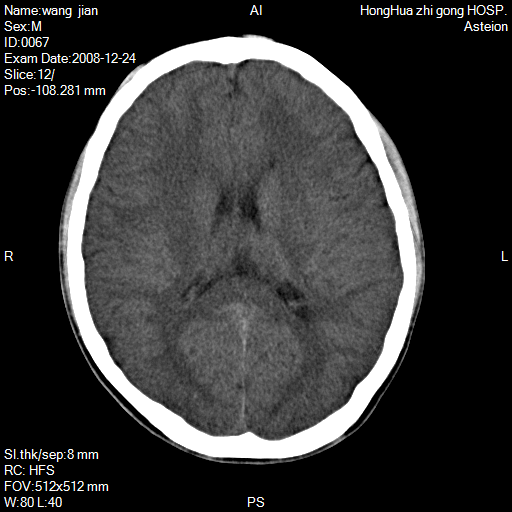

标题: CT17293:男/15/癫痫/小时有外伤史 [打印本页]

标题: CT17293:男/15/癫痫/小时有外伤史

15岁松果体钙化了,建议进一步mri检查以排松果体瘤

大脑镰脑膜瘤?

左侧顶叶镰旁见低密度影,建议mr检查。

左顶叶大脑镰旁稍低不均质密度影,建议增强ct或mr检查

感觉额颞顶叶部分脑回很细碎,不排除异常,如小多脑回畸形,左侧中央旁小叶区确有圆形低密度区,不知是否病灶,建议mr检查

左侧顶叶镰旁见低密度影,建议mr检查。好象是伪影。

也看着了在左镰旁异常低密度灶,是占位的样子,要进一步检查清楚。